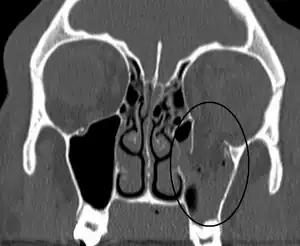

Thin cut (2-3mm) CT scan with axial and coronal view is the optimal study of choice for orbital fractures.[14][15]

Plain radiographs, on the other hand, do not have the sensitively capture blowout fractures.[16] On Water's view radiograph, polypoid mass can be observed hanging from the floor into the maxillary antrum, known as the "teardrop sign", as it usually is in shape of a teardrop. This polypoid mass consists of herniated orbital contents, periorbital fat and inferior rectus muscle. The affected sinus is partially opacified on radiograph. Air-fluid level in maxillary sinus may sometimes be seen due to presence of blood. Lucency in orbits (on a radiograph) usually indicate orbital emphysema.[4]

| An orbital blowout fracture of the floor of the left orbit. | |